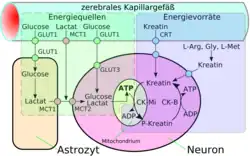

Die Hauptaufgabe der Astrozyten sind jedoch die selektive Versorgung der Neuronen mit Nährstoffen sowie die Regulation der extrazellulären Ionenkonzentrationen.[57][59] Ein Großteil des im Gehirn vorhandenen Cholesterols wird von Astrozyten produziert. Cholesterol kann die Blut-Hirn-Schranke nicht passieren, weshalb es lokal innerhalb des Gehirns synthetisiert werden muss. Im Gehirn befinden sich etwa 25 % des Cholesterols des gesamten Körpers; im Wesentlichen im Myelin, das die Axone der Neuronen ummantelt.[60]

Eine spezielle Form der Diffusion durch die Zellmembran der Endothelien ist die erleichterte Diffusion (engl. facilitated diffusion). Lebenswichtige Nährstoffe wie Glucose und viele Aminosäuren sind zu polar und zu groß, um auf den bisher geschilderten Transportwegen in ausreichender Menge dem Gehirn über die Blut-Hirn-Schranke zur Verfügung gestellt zu werden. Für diese Moleküle gibt es in der Zellmembran ein spezielles Transportsystem: den sogenannten Carrier-vermittelten Transport. Beispielsweise wird die D-Glucose über den GLUT-1-Transporter in das Gehirn transportiert. Die Dichte der GLUT-1-Transporter ist auf der abluminalen Seite der Endothelien viermal höher als auf der luminalen, das heißt der zum Blut hin gerichteten, Seite.[120] Der Transport wird nur durch ein Konzentrationsgefälle ermöglicht und benötigt selbst keine Energie.

Neben der in relativ großen Mengen vom Gehirn benötigten D-Glucose gibt es außer GLUT-1 eine Reihe von weiteren speziellen Transportern. Sehr viele dieser Transporter sind aus der Familie der Solute Carrier (SLC), darunter beispielsweise MCT-1 und MCT-2, die eine Reihe von kurzkettigen Monocarbonsäuren – unter anderem Lactat, Pyruvat, Mevalonat, verschiedene Butyrate und Acetat – transportieren. SLC7 transportiert kationische Aminosäuren (Arginin, Lysin und Ornithin). Vom Modellorganismus Maus sind bisher 307 SLC-Gene bekannt. Davon werden über 200 im Choroid plexus und in anderen Gehirnbereichen exprimiert. An der Blut-Hirn-Schranke der gleichen Art wurden bisher allerdings nur 36 nachgewiesen. Etwa 70 % von den 36 haben Genprodukte, die am Transport von Nährstoffen, Vitaminen, Hormonen und Spurenelementen beteiligt sind. Besonders stark sind an der Blut-Hirn-Schranke die Thyroid-Transporter SLC16a2 und SLCO1c1, der Sulfat-Transporter SLC13a4, der L-Ascorbinsäure-Transporter SLC23a2, der Aminosäure-Transporter SLC 38a3 und der Folat-Transporter SLC19a1 exprimiert.[121] Ascorbinsäure (Vitamin C) wird in oxidierter Form über die Glukosetransporter dem Gehirn zugeführt.[122]